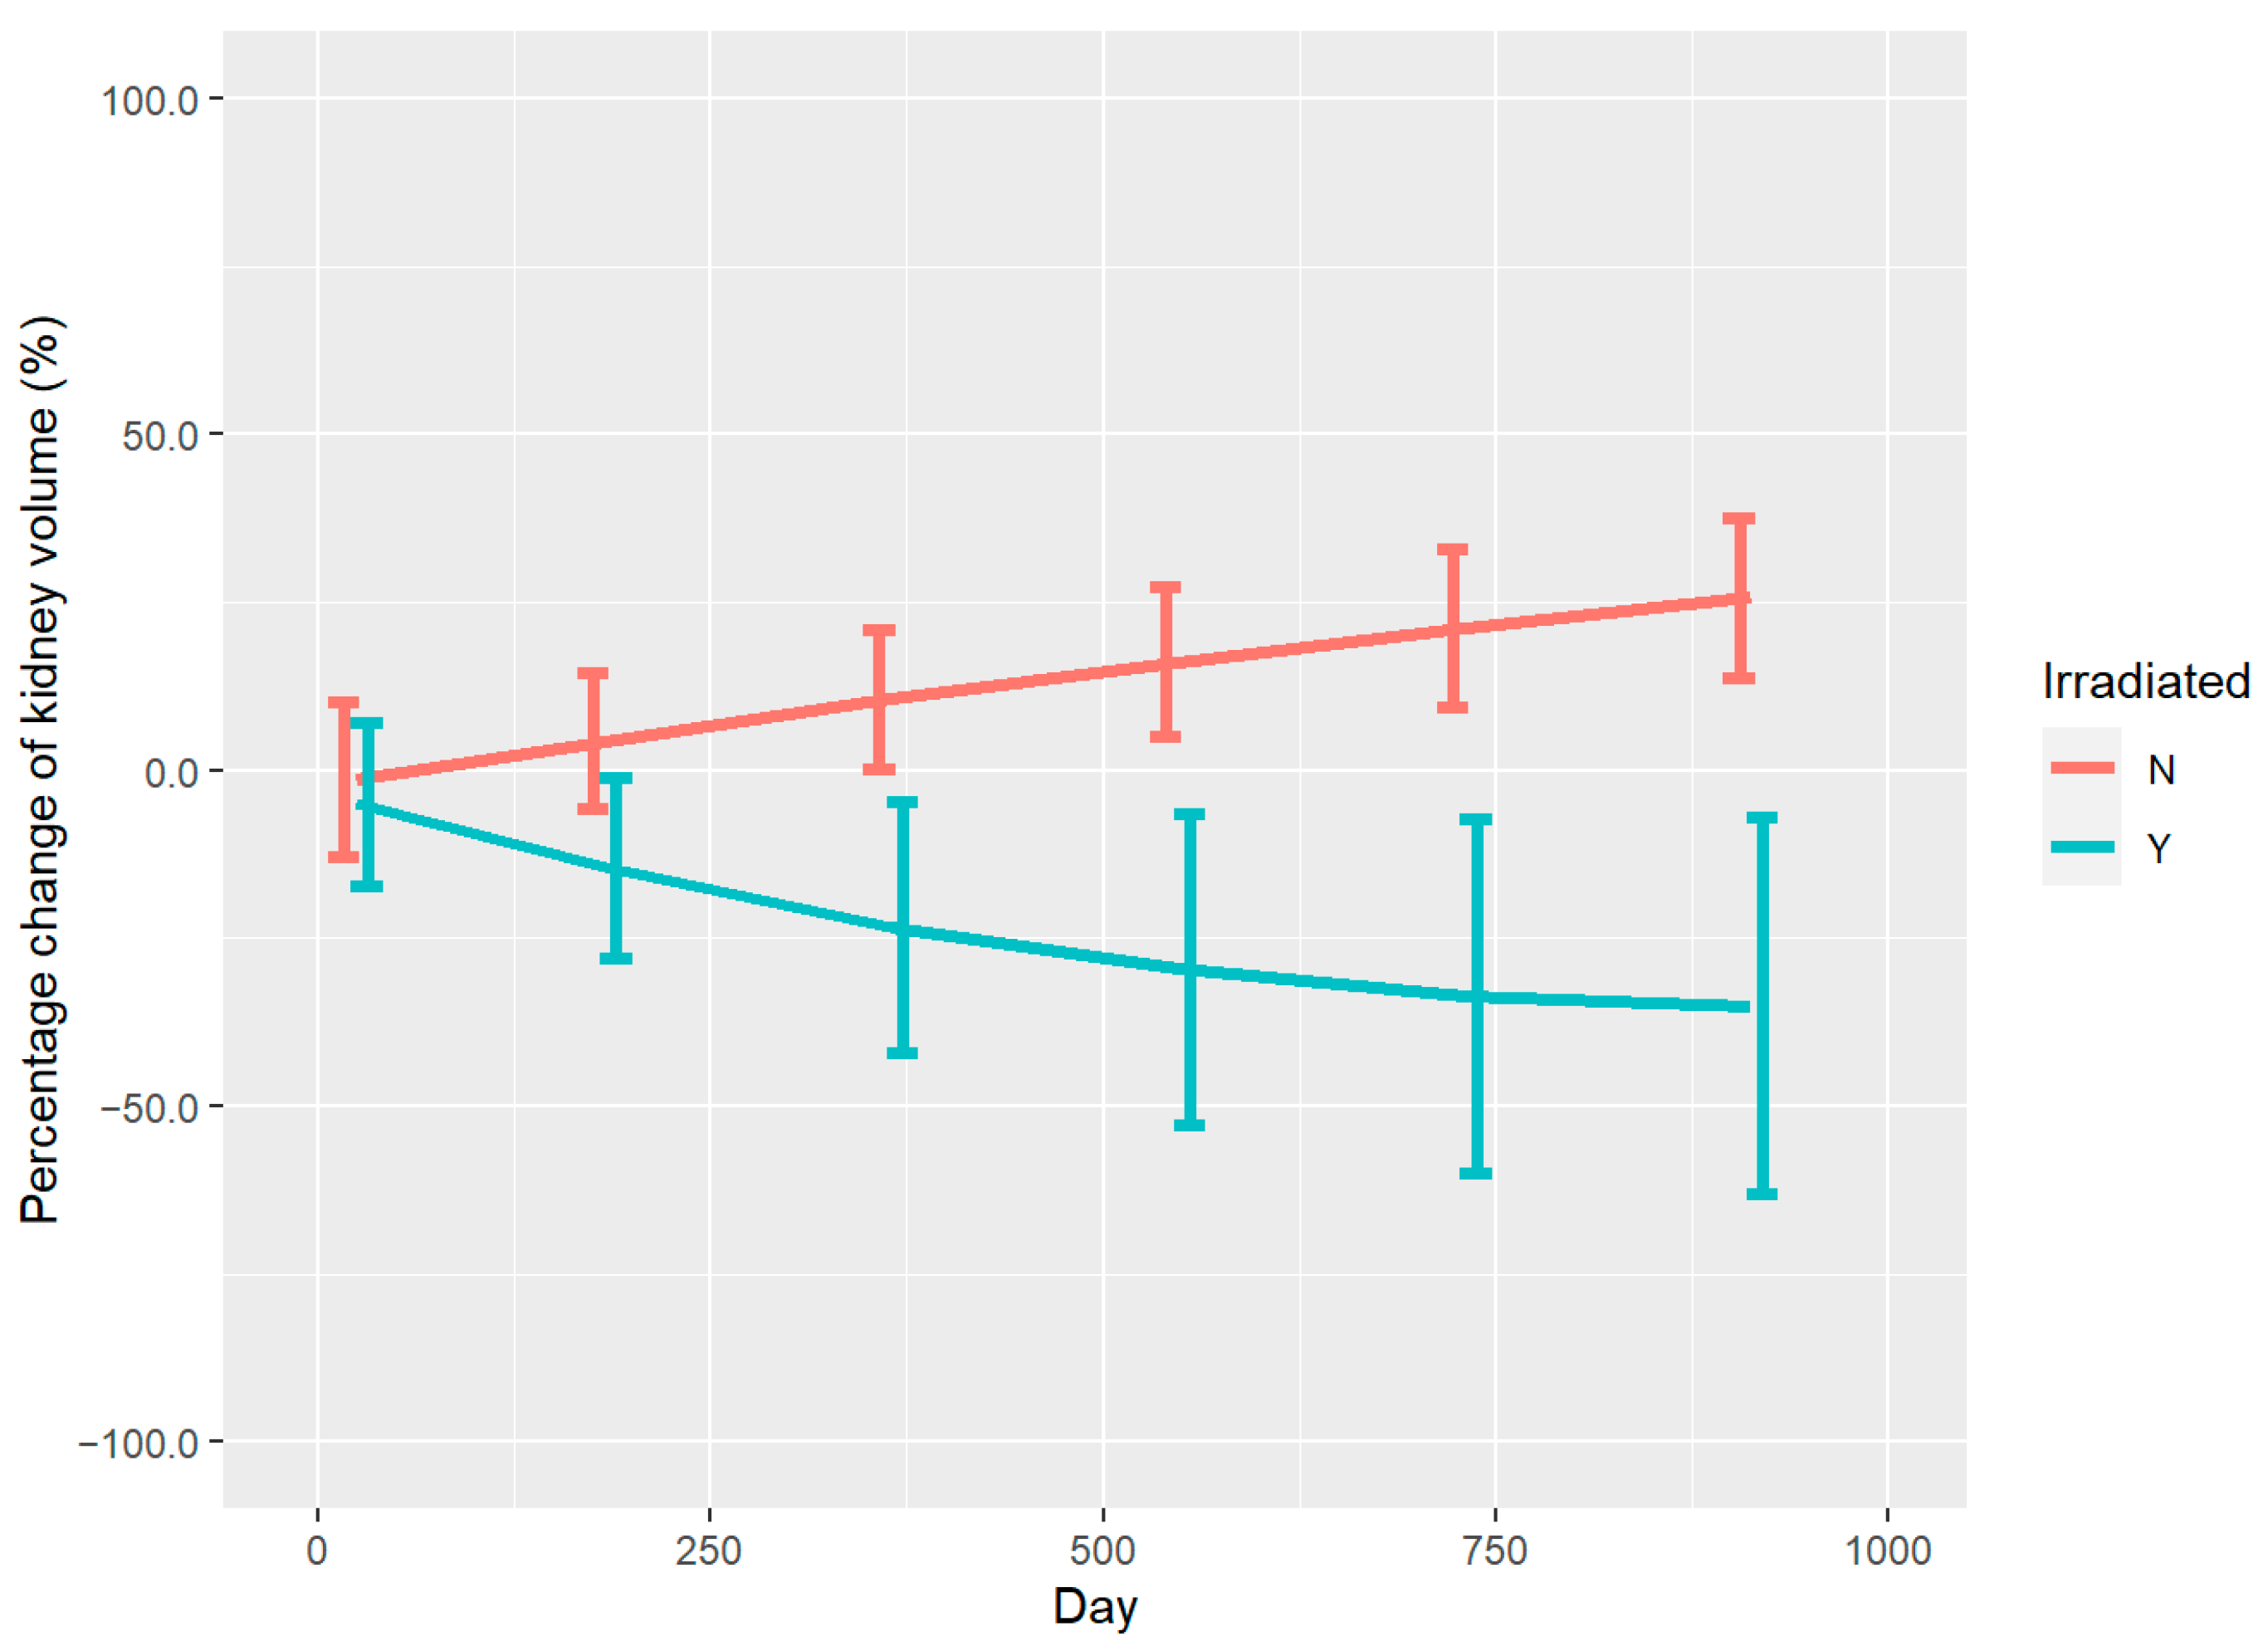

3.2. Renal Volume Changes and DVH Analysis